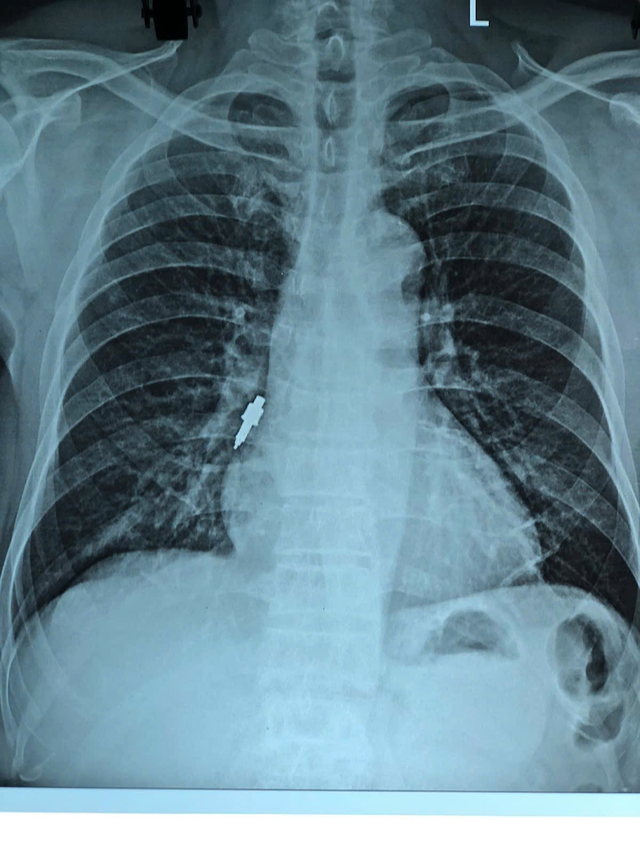

În urma investigațiilor pacientului, s-a aflat că, în urmă cu aproximativ două săptămâni, acesta fusese supus unei proceduri de implant la o clinică stomatologică privată. În timpul procedurii, medicul dentist l-a informat că a pierdut un instrument, dar nu a putut determina unde a căzut. După ce s-a întors acasă, pacientul a avut o tuse ușoară care a durat mult timp și s-a agravat treptat, așa că s-a dus la spital pentru examinare. Rezultatele radiografiei au arătat că pacientul avea un obiect străin în bronhia dreaptă. Procesul de endoscopie de urgență în cazul menționat mai sus a întâmpinat multe dificultăți, deoarece obiectul străin era mare, alunecos și blocat adânc în bronhie.

Instrumente dentare prelevate din bronhiile pacientului

Un obiect străin a fost blocat adânc în bronhia pacientului.